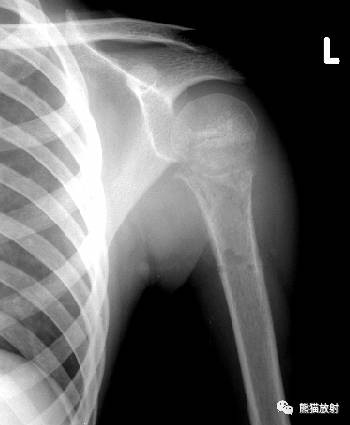

↓ 肱骨近端骨巨细胞瘤

II型 ↓ 肱骨骨髓炎(金葡菌)